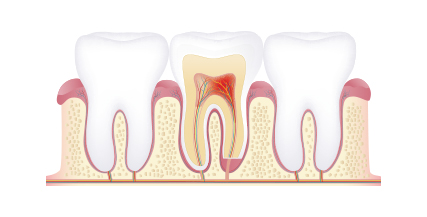

충치는 감염 속도가 빠르고, 신경관이나 치근 등으로 세균이 확산되어 더 큰 질환을 일으킬 수 있습니다. 강서모아치과는 정확한 진단과 주기적인 관찰을 통하여 적시에 충치를 진단하고, 필요한 치료만을 진행합니다.

충치 단계에 따라서

가장 치아를 살릴 수 있는 치료 방법을 제안드립니다.

치아 겉면인 법랑질의 충치로 통증이 거의 없습니다.

정기검진, 레진

법랑질 안쪽에 있는 상아질까지 충치가 진행되어 뜨겁거나 차가운 음식을 먹으면 시린 증상이 나타납니다.

레진, 인레이

상아질 안쪽 신경까지 염증이 진행되어 극심한 통증으로 참기 어려운 정도가 됩니다.

신경치료 + 크라운

치아 내부에 있는조직이 괴사되고, 뿌리 주변의 염증으로 인하여 뼈가 점차 소실됩니다.

고난이도 보존치료, 임플란트